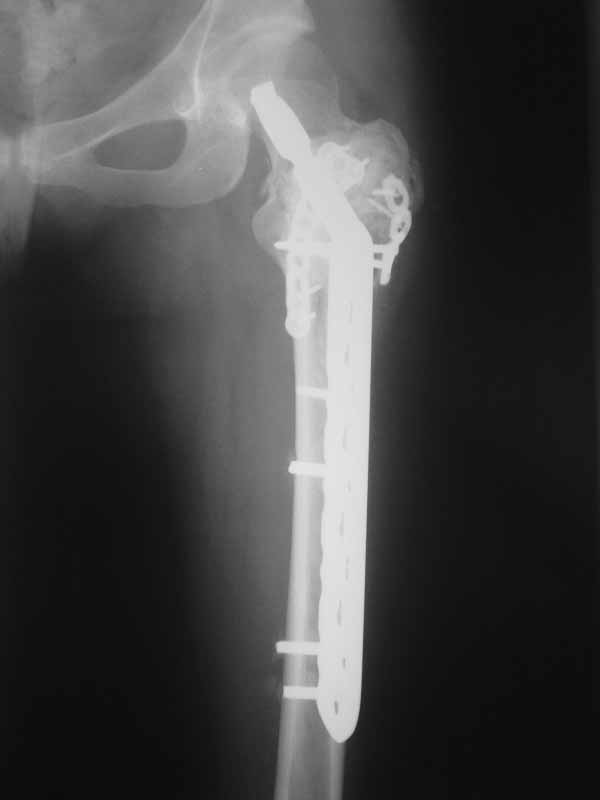

Молодая пациентка 23 лет. Травма в результате падения с высоты своего роста. Упала 2 дня назад доставлена к нам вот с такой картиной. Из анамнеза - боли беспокоят в течении полугода, постоянные. Никуда не обращалась. Уважаемое сообщество подскажите - ОБК?, Фиброзная дисплазия?, Киста?. Тактика ведения?. Девушка молодая!!!

А по пациентке:Обследования провели в легких чисто, лабораторно - без особенностей. Выполнили МРТ - костная киста, однокамерная. Оперирована - створчатая остеотомия, удаление кисты, костная пластика аутокостью с гребня подвздошной кости, остеосинтез DHS со сприральным клинком, створка фиксирована пластинами монокортикально.

Макроскопически - слизеподобное содержимое темно-бурого цвета, отдали на гистологию.